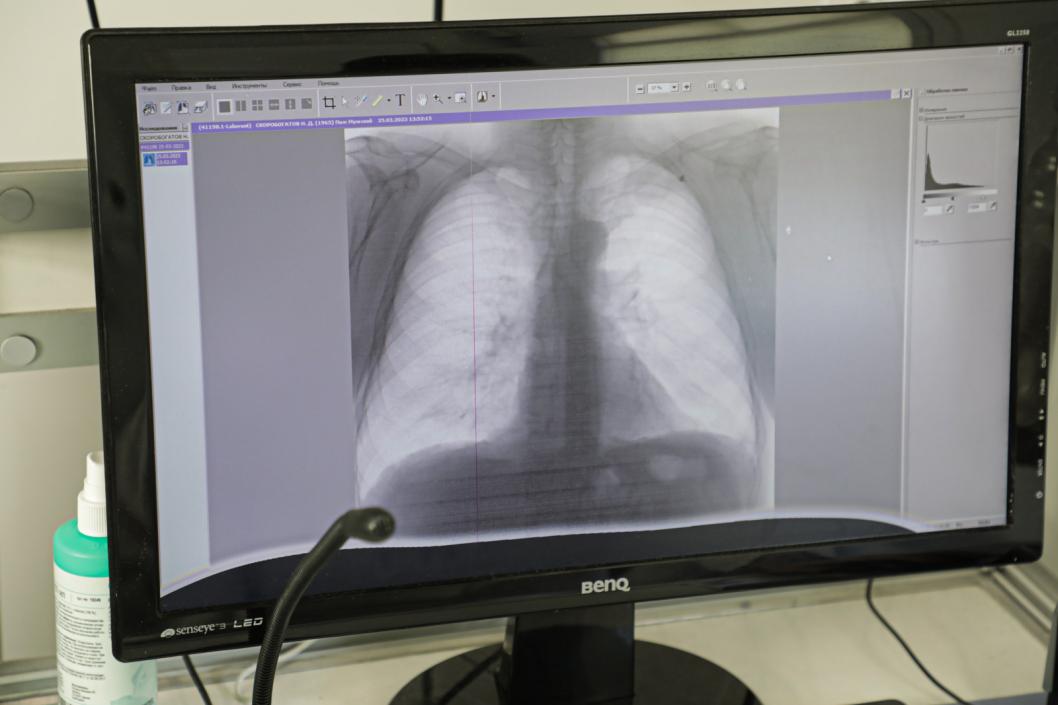

Фото Сергея Куликова

Профилактикой страшной болезни является своевременная ежегодная флюорография. Эта несложная процедура позволит сразу же заметить отклонения от нормы. Далее подозрения нужно будет подтвердить или опровергнуть более тщательным исследованием.